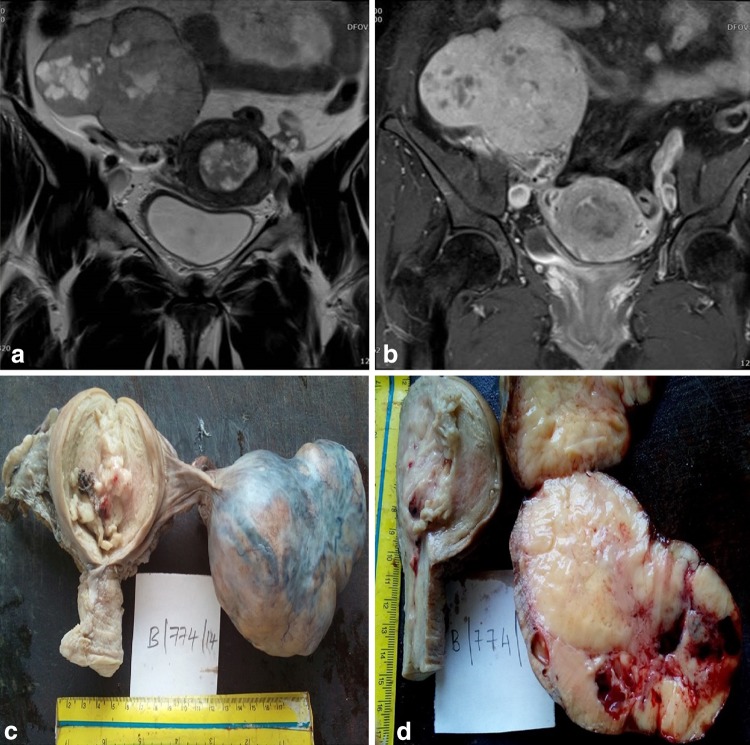

A 55-year-old female, gravida 4, para 4, sought consult for the assessment of heaviness in the lower abdomen and postmenopausal bleeding. She had attained menopause 5 years back and had no significant past or family history. On examination, a 12 × 10 cm firm mass was palpable in the hypogastrium extending to right iliac, lumbar, and umbilical regions. Vaginal examination revealed a uniformly enlarged uterus of 10–12 weeks and a right adnexal mass. Ultrasound abdomen showed a right adnexal mass and a bulky uterus with thickened endometrium. Magnetic resonance imaging showed a T1 hypointense and T2 mixed-intense (solid and cystic) lobulated mass involving the right ovary of 9.1 × 7.6 cm in size. Bulky uterus showing grossly thickened endometrium with breach in junctional zone was also noted (Fig. 1a). Post-contrast study showed significant enhancement of right ovarian mass and uterine endometrium, and a diagnosis of neoplastic lesion was made from imaging studies (Fig. 1b). Endometrial aspiration revealed endometrioid adenocarcinoma. On staging laparotomy, a 10 × 11-cm-sized solid right ovarian tumor and a bulky uterus were seen. The left ovary, fallopian tube, intestines, liver, biliary tract, pancreas, and omentum were normal with minimal ascites. Total abdominal hysterectomy with bilateral salphingoopherectomy, infracolic omentectomy, and pelvic lymphadenectomy was performed.

Fig. 1.

a T2 coronal magnetic resonance sequence shows uterus with grossly thickened endometrium and breach of junctional zone. Large right ovarian mass with solid and cystic areas is also appreciated. b T1 fat sat coronal post-contrast magnetic resonance sequence shows heterogenous enhancement of endometrial cavity and diffuse enhancement of right ovarian mass with few non-enhancing cystic areas. c Gross photograph of uterus and cervix with enlarged right ovarian mass having nodular surface. Cut section of the uterus showing exophytic growth in endometrial canal. d Cut section of the right ovary showing gray white nodules with cystic areas with compressed normal parenchyma at the periphery

On gross examination, the right ovary was found to be enlarged and measured about 9 × 7.5 × 5 cm with nodular surface and no capsular breech (Fig. 1c). The cut section revealed a solid gray white tumor with areas of hemorrhage, cysts, and compressed ovarian parenchyma at the periphery (Fig. 1d). An exophytic growth of 4 × 2 cm in size was seen at the fundal and posterior walls of the endometrial canal with no gross invasion of the myometrium (Fig. 1c). Left ovary, omentum, and bilateral fallopian tubes were grossly unremarkable. Microscopy sections from the right ovarian mass showed a cellular tumor composed of multiple nodules of interlacing spindle-shaped cells in fascicles with no atypia, and a mitotic count ranging from 0 to 1 per 10 high-power fields consistent with fibroma. No thecomatous elements were found in the tumor even on performing fat stain. Interspersed among the bland stromal cells were small nests of cells with grooved oval nucleus and minimal cytoplasm, comprising <5 % of total tumor area (Fig. 2a). These cells were strongly immunoreactive for inhibin (Fig. 2b). The endometrial growth showed features of endometrioid adenocarcinoma (Grade 1) (Fig. 2c) and multiple foci of complex hyperplasia with atypia of endometrial glands (Fig. 2d). Focal invasion into the myometrium involving less than 2 % of the thickness was noted. The omentum, lymph nodes, right ovary, and both fallopian tubes were free from tumor. A final diagnosis of well-differentiated endometrioid adenocarcinoma (Grade I) of the uterus with fibroma and minor sex cord elements of right ovary was made. The patient did not receive radiotherapy postoperatively and is free from recurrence or distant metastasis since one year.